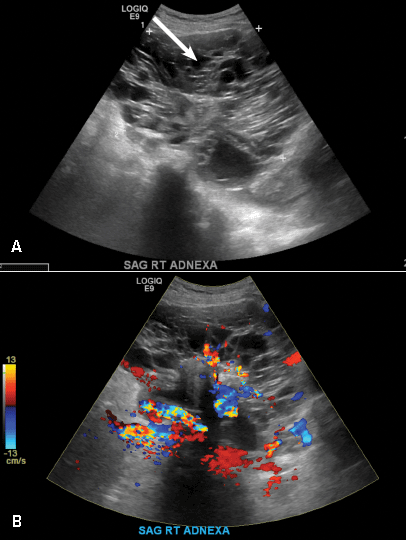

(B) Hemorrhagic cyst CORRECT

This type of cyst is well circumscribed and hypoechoic, with posterior acoustic enhancement and demonstrates a lacy reticular pattern of internal echoes due to fibrin strands (long arrow). The internal echoes also may be solid appearing with concave margins (short arrow) due to retractile hemorrhagic clot.1 The absence of internal vascular flow on color Doppler helps differentiate it from the solid components seen in ovarian neoplasm.

Hemorrhagic cysts. (A) Transvaginal pelvic ultrasound of the left ovary demonstrates a well-circumscribed hypoechoic cyst with posterior acoustic enhancement and demonstrates a lacy reticular pattern of internal echoes (long arrow). (B) Transvaginal pelvic ultrasound of the right ovary demonstrates a well-circumscribed hypoechoic cyst with solid appearing retractile hemorrhagic clot with concave margins (short arrow) and no vascular flow on color Doppler.